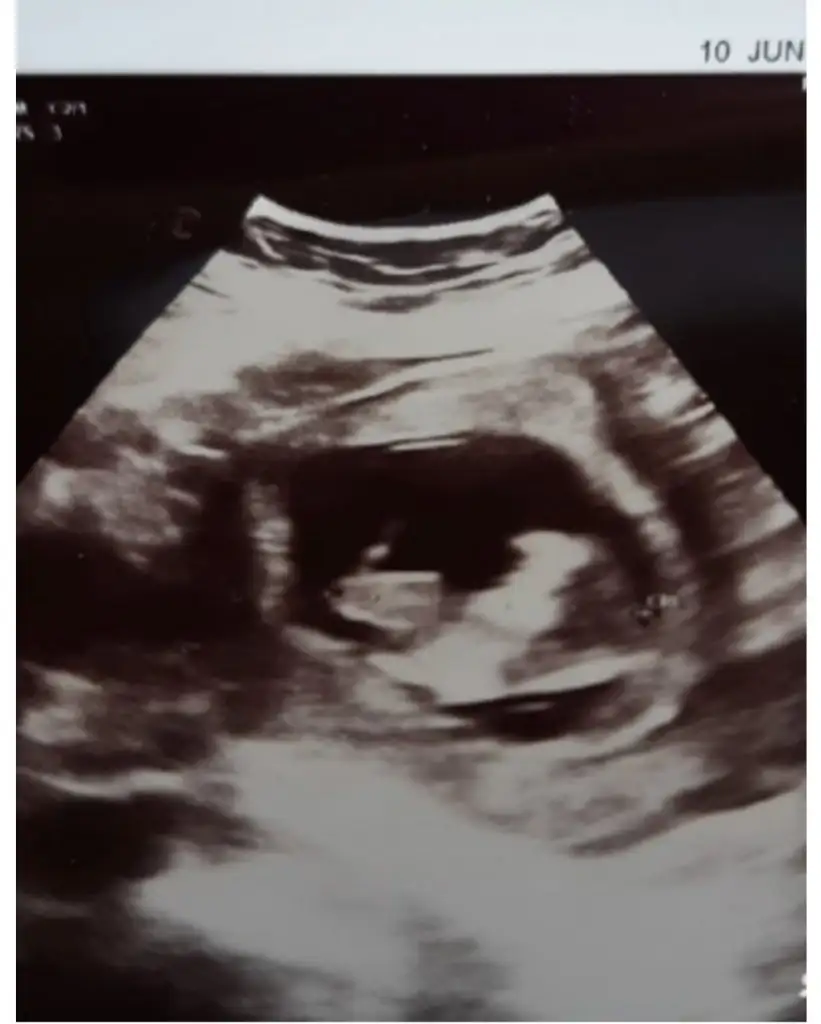

Bizim bebek byle duruyor 18 haftalık oldum ve cinsiyetını öğrenemedim.sizce nedirSelam Kızlarbir çok kişi gruplardan beni bilir. Yine yetiştim imdatlara

5 ve 14. haftaya kadar olan ultrason fotolarınızı paylaşın. Vajinadan mı yoksa karından mı çekildiğini ve kaç haftalık olduğunu da mutlaka belirtin.